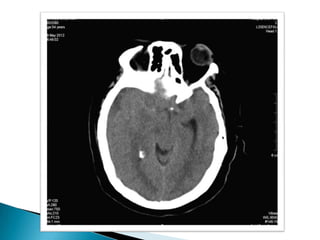

   Imagen hiperdensa en región fronto-

temporo-parietal izquierda, con

desplazamiento de la línea media y

borramiento de ventrículos laterales

compatible con hemorragia subdural.

   Hiperdensidad compatible con hemorragia

subaracnoidea.

TC cerebro: Presencia de trazo fracturario a nivel occipital, temporo-parietal izquierda y hundimiento de región derecha.  Imagen hiperdensa en región fronto- temporo-parietal izquierda, con desplazamiento de la línea media y borramiento de ventrículos laterales compatible con hemorragia subdural.  Hiperdensidad compatible con hemorragia subaracnoidea.  Cefalohematoma que recorre toda la zona occipital y temporal